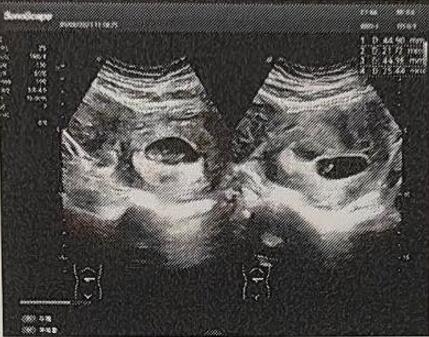

2023年2月,行宫腔镜检查处理子宫内膜息肉;替代方案移植2个胚胎,成功双胎妊娠并顺利“毕业”!